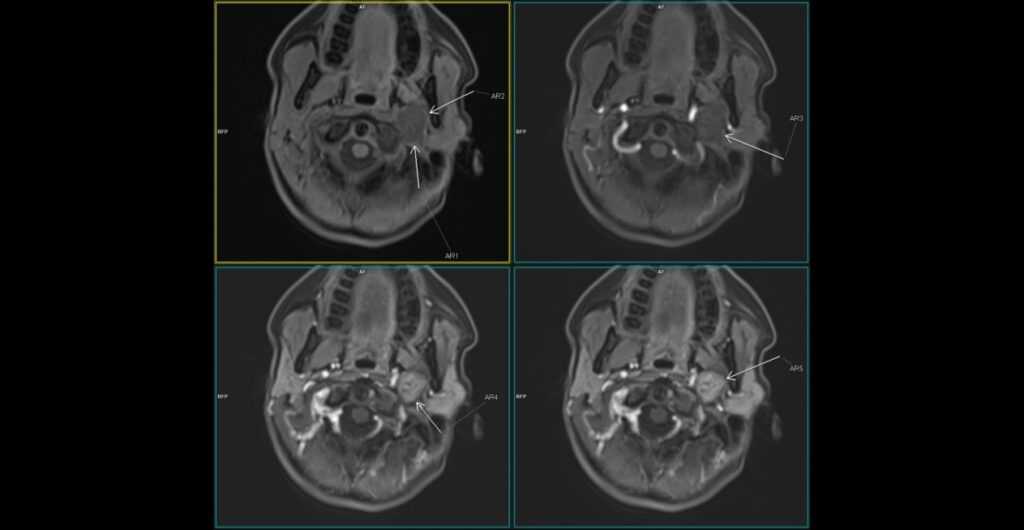

Discuţie caz nr 130: examinare efectuată pentru suspiciune de dilatație anevrismală a aortei ascendente; achiziția a fost realizată cu sincronizare ECG pentru vizualizare optimă a valvei aortice și a peretelui aortic și surpriza a fost un arc aortic la dreapta cu aortă descendentă toracică la dreapta și o dilatație anevrismală / diverticul posterior de trahee și esofag și anterior de coloana vertebrală din care are origine arteră subclavie stânga (Diverticulul Kommerell).

DE LUAT ACASĂ!!! Achiziția cu sincronizare ECG la examinarea AngioCT aortă toracică este indicat / obligatoriu sa fie utilizată la pacienții care sunt trimiși la examinare CT pentru evaluarea aortei toracice. Diverticulul Kommerell se referă de obicei la configurația bulboasă a originii unei artere subclaviculare stângi aberante în contextul unui arc aortic drept. Cu toate acestea, a fost descrisă inițial ca o protuberanță diverticulară la originea unei artere subclaviculare drepte aberante cu un arc aortic stâng și se observă și în arterele vertebrale drepte aberante (arteria lusoria vertebrală).